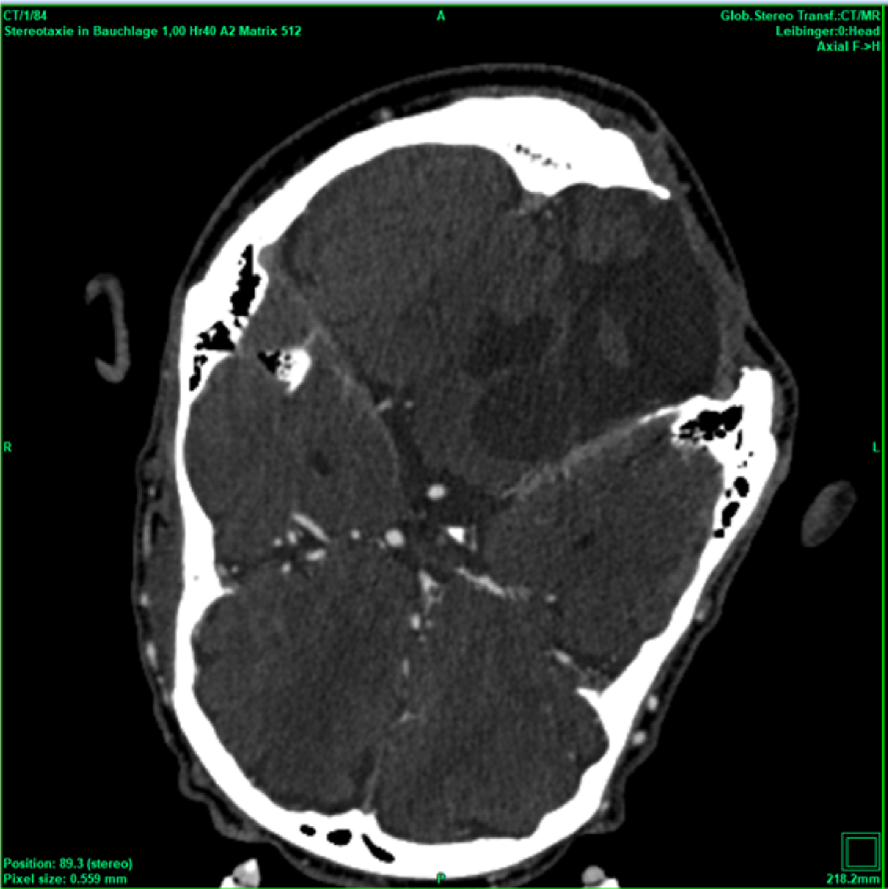

The patient declined open surgery; therefore, stereotactic aspiration of the cyst was offered as an alternative. Following aspiration, the patient’s condition improved for approximately three months before gait disturbances recurred. To facilitate future management, the placement of a Rickham reservoir was considered. Up to that point, all stereotactic cyst aspirations and the initial Rickham reservoir placement had been performed with the patient in the prone position via a right infratentorial approach. During the most recent open resection, a large infratentorial craniectomy had been performed (Figure 2).

Figure 2 Large bony defect after right suboccipital craniectomy (patient in prone position!).